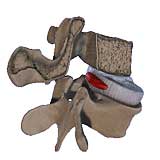

Entfernung eines Bandscheibenvorfalls:

Das natürlich vorgegebene Fenster zwischen zwei Wirbelbögen wird zuvor erweitert, der Nervenwurzelsack mit der abgehenden Nervenwurzel wird mit einem kleinen Hacken beiseite gehalten. Hiernach wird in den meisten fällen eine Ausräumung des Bandscheibenfaches erfolgen. |